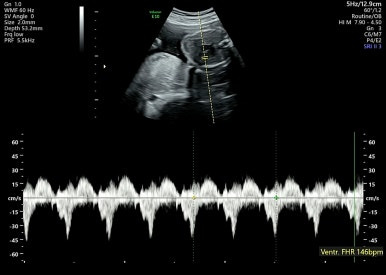

9주 1일차

젤리곰 같은 태아를 볼 수 있다! 벌써 손발이 생겨 움직이는 모습이 너무 신기하다.

이 시기는 평소보다 심장이 원래 빨리 뛰는 시기이다.